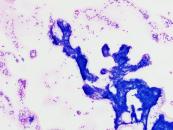

第40回日本臨床細胞学会九州連合会学会(大分)スライドカンファレンス症例5

種別:消化器・口腔

出題:中園 裕一、松尾 貴弘、後藤 優加 独立行政法人国立病院機構別府医療センター

| 年齢 | 40代 | 性別 | 女性 |

| 採取部位 | 膵 | 採取方法 | 穿刺吸引細胞診 |

| 検体処理法 | 従来法 |

既往歴:特記事項なし

現病歴:発熱、肝酵素上昇(伝染性単核球症疑い)の精査で施行された各種画像検査(腹部エコー、CT、MRI)にて膵頭部に10mm大の病変が描出された。精査のため、同部に対しEUS-FNAによる検体採取が施行された。

| 正解 | 4.Solid pseudopapillary neoplasm |

▼選択肢及び投票結果

| 1.Invasive ductal carcinoma | 2件 | (1.9%) | |

| 2.Acinar cell carcinoma | 10件 | (9.5%) | |

| 3.Neuroendocrine neoplasm | 8件 | (7.6%) | |

| 4.Solid pseudopapillary neoplasm | 73件 | (69.5%) | |

| 5.Intraductal tubulopapillary neoplasm | 12件 | (11.4%) | |

| 投票総数 | 105件 | (100%) |